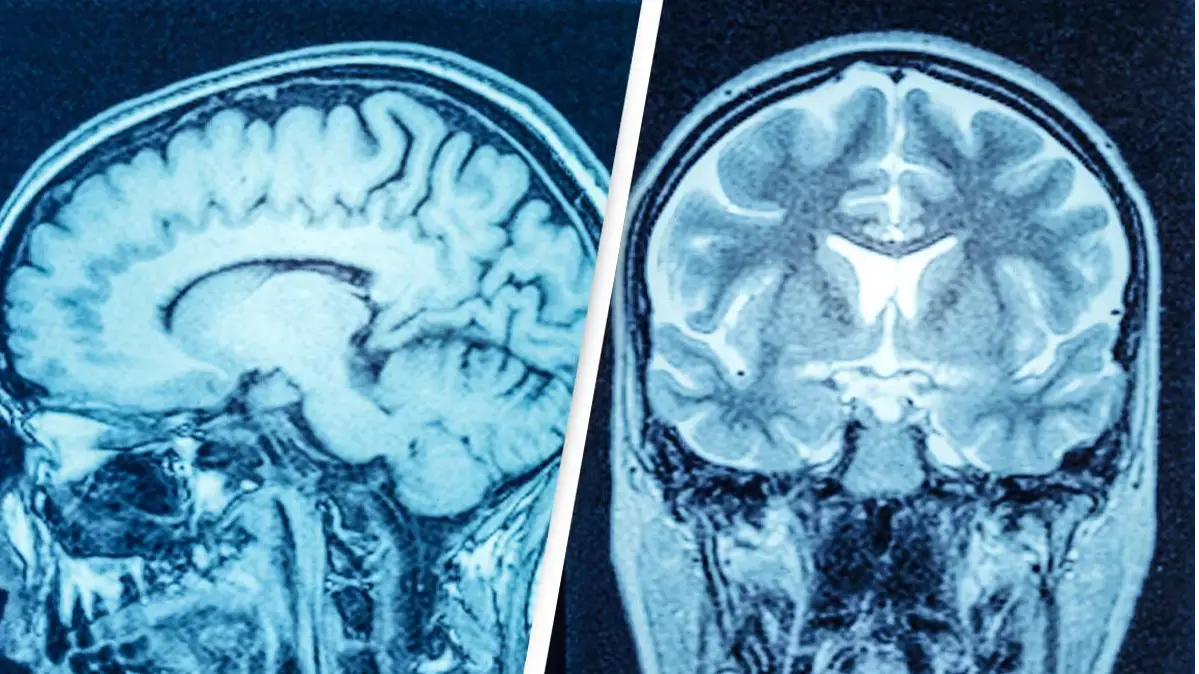

So, when doctors scanned his brain to access the cause of his unexplained leg weakness, they were surprised to find that he had an enormous fluid-filled chamber.

However, this man's brain fluid built up, which left him with a massive deposit of liquid and very little brain matter.

Speaking about the case, Feuillet confirmed that the fluid buildup had led to a significant reduction in brain matter: "It is hard for me [to say] exactly the percentage of reduction of the brain, since we did not use software to measure its volume. But visually, it is more than a 50 to 75 percent reduction.

"The whole brain was reduced – frontal, parietal, temporal, and occipital lobes – on both left and right sides. These regions control motion, sensibility, language, vision, audition, and emotional and cognitive functions," Feuillet went on to tell New Scientist.